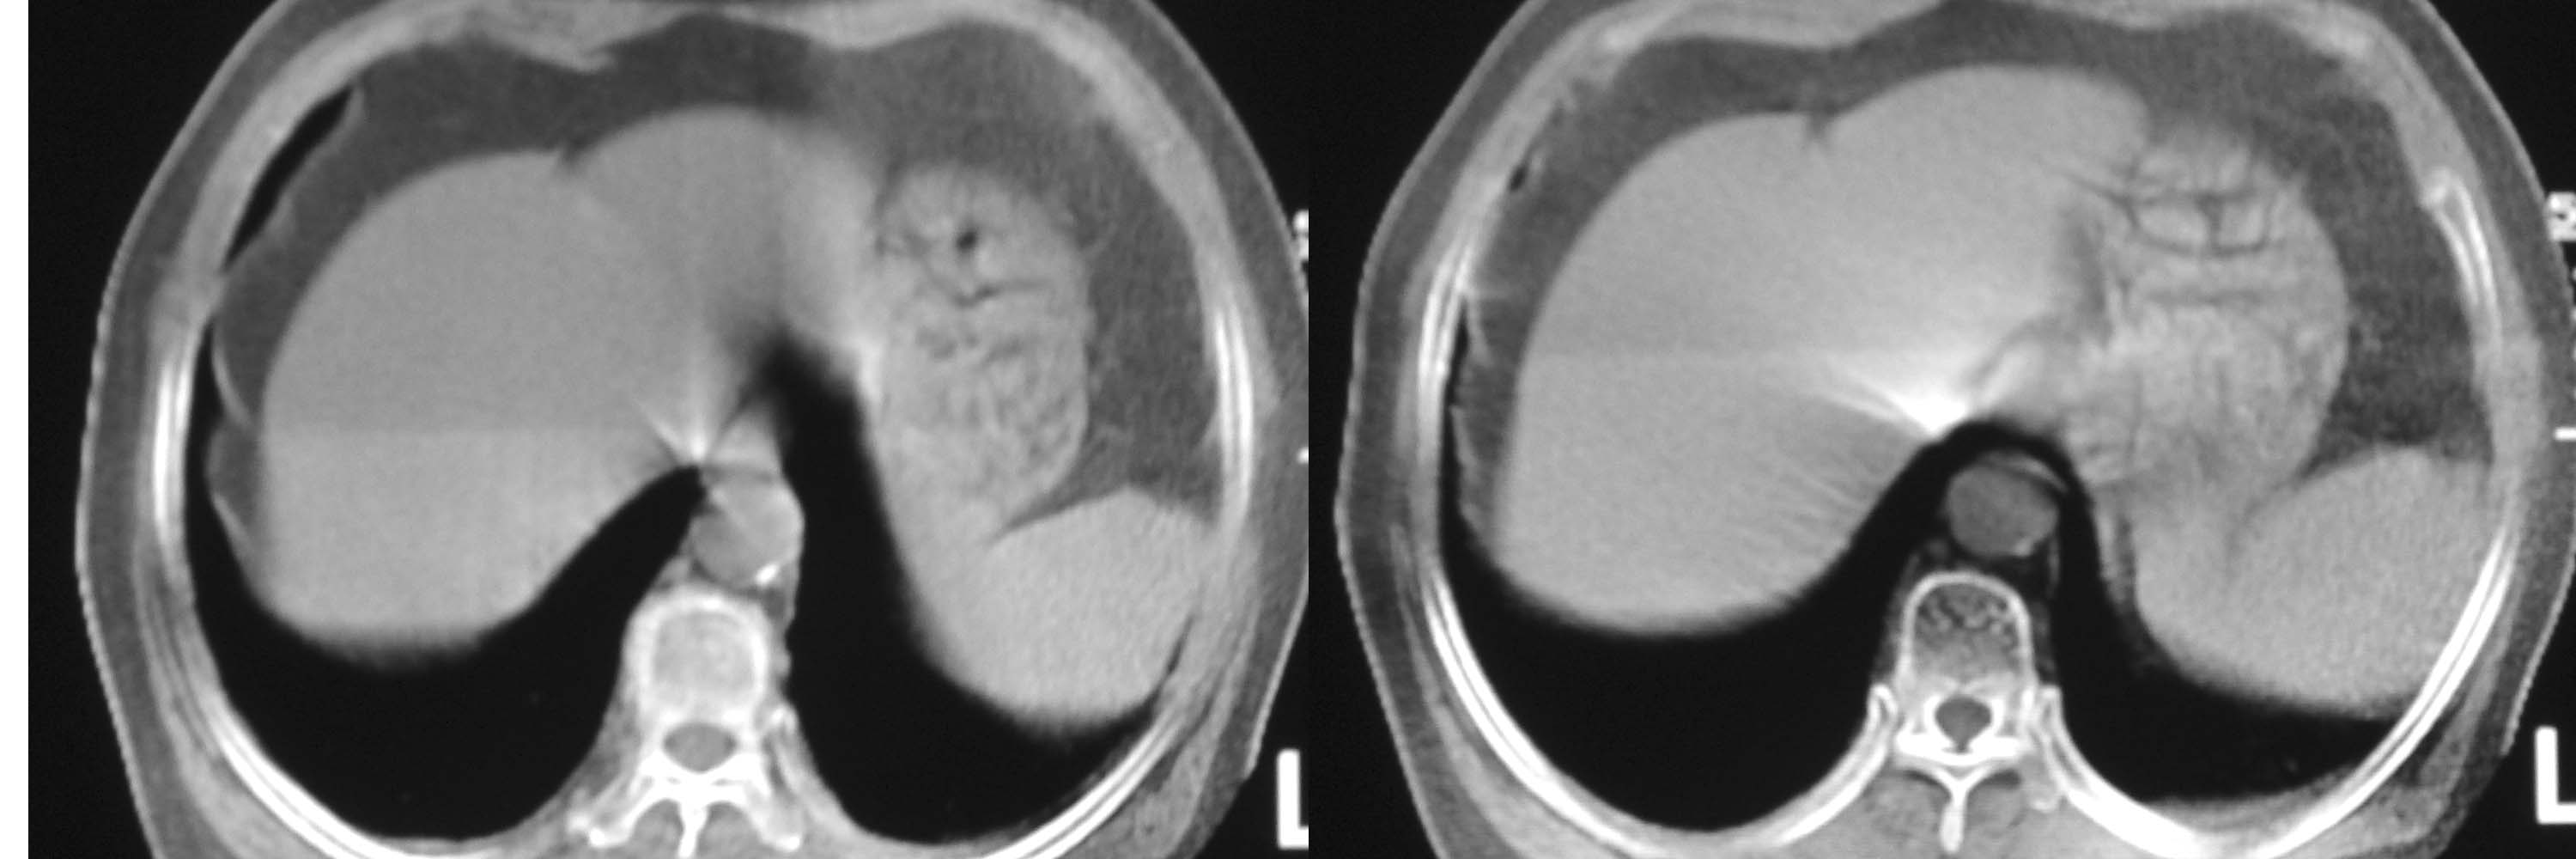

女78岁咳嗽咳痰无咳血平片报右上肺不张、慢支、肺气肿、请老师们帮忙看看,箭头所指是什么?是占位吗?有肺气肿吗?谢谢

箭头所指考虑血管影;纵隔内及双肺门区多发淋巴结钙化;不支持肺气肿。

箭头所指考虑血管影(头臂血管);纵隔内及双肺门区多发淋巴结钙化;不支持肺气肿。